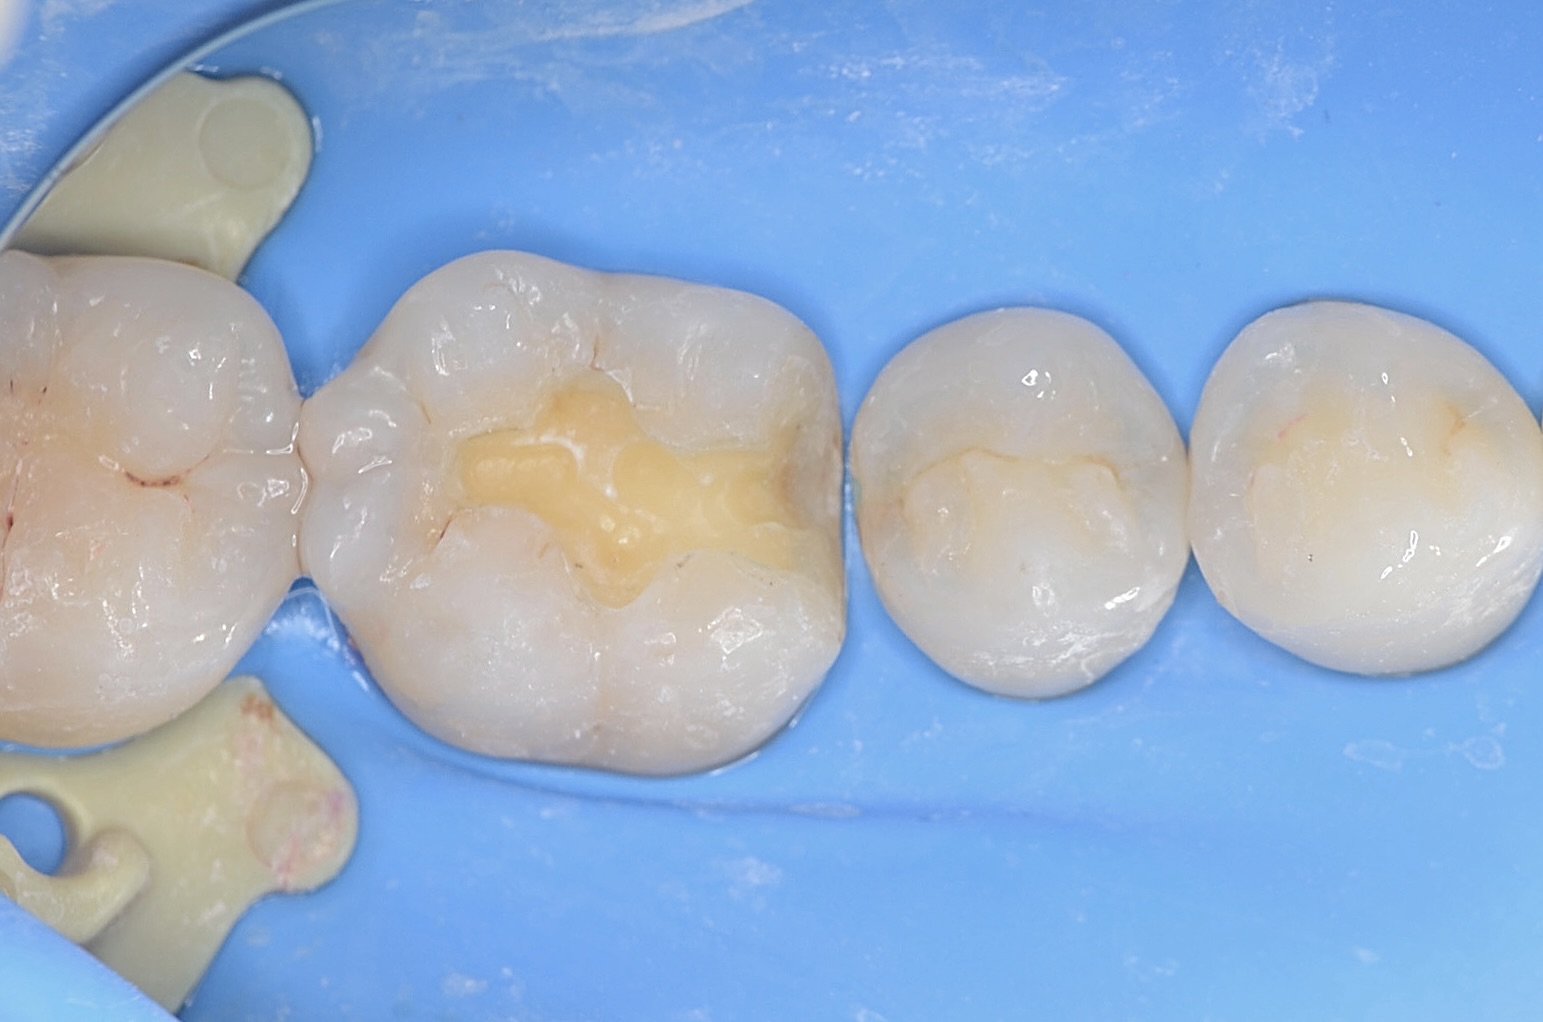

ジルコニアインレーの接着操作

唾液や血液から歯面が汚染されるのを防ぎ、乾燥状態を保つラバーダムは、接着力を向上させるためにも大切なアイテムです。 接着剤が隣の歯にかからないようにテープで養生します。 -

レジンセメント硬化

ジルコニアインレーを光硬化型のレジンセメントにて接着します。 -